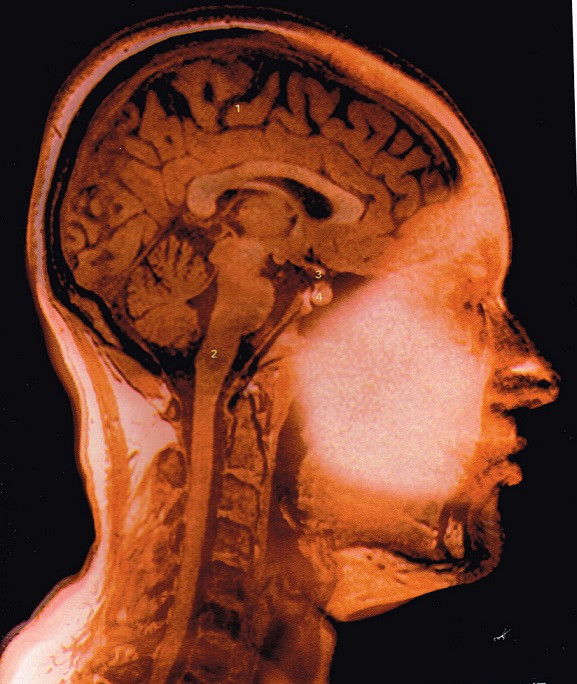

表皮そして真皮の下にある皮膚を支えている、皮筋=お顔のインナーマッスルへアプローチしていくもので

具体的には、筋芽細胞を太く強くし皮筋を活性化するために

’HSP’ヒートショックプロテイン

に注目したお手入れで

HSP(ヒートショックプロテイン)を活性化させ、さらにその温熱効果により、3ステップで徐々に皮筋(インナーマッスル)に働きかけてリフトアップしていくものです